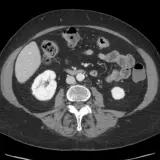

Over 2,100 interactive radiology cases, curated by radiologists for your level of training. Scroll, window, and view cases full screen — just like on PACS. Click linked findings in each writeup to jump straight to them on the image. Cases include sample reports, a focused discussion section, original illustrations, and videos.

完全交互式病例,配备您在 PACS 上期待的各项工具——滚动、调窗、缩放、平移、测量、ROI 和全屏模式。

丰富的标注直接在病例图像上突出关键发现。点击病例讲解中的关联发现,即可跳转至其在扫描上的精确位置。